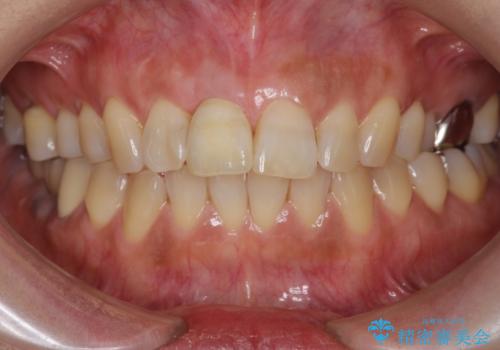

前歯のインプラント治療について

前歯のインプラントを審美的に仕上げるには、インプラント周囲に十分な骨の量と厚みのある歯肉、そして埋入位置の精密な位置付けが重要です。